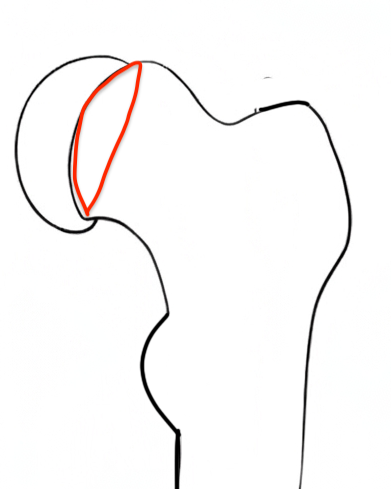

Cam FAI

Mechanism

Epiphysis heals in a posterior and inferior position with moderate - severe slips

Abnormal contact of relatively anterior neck on the acetabulum